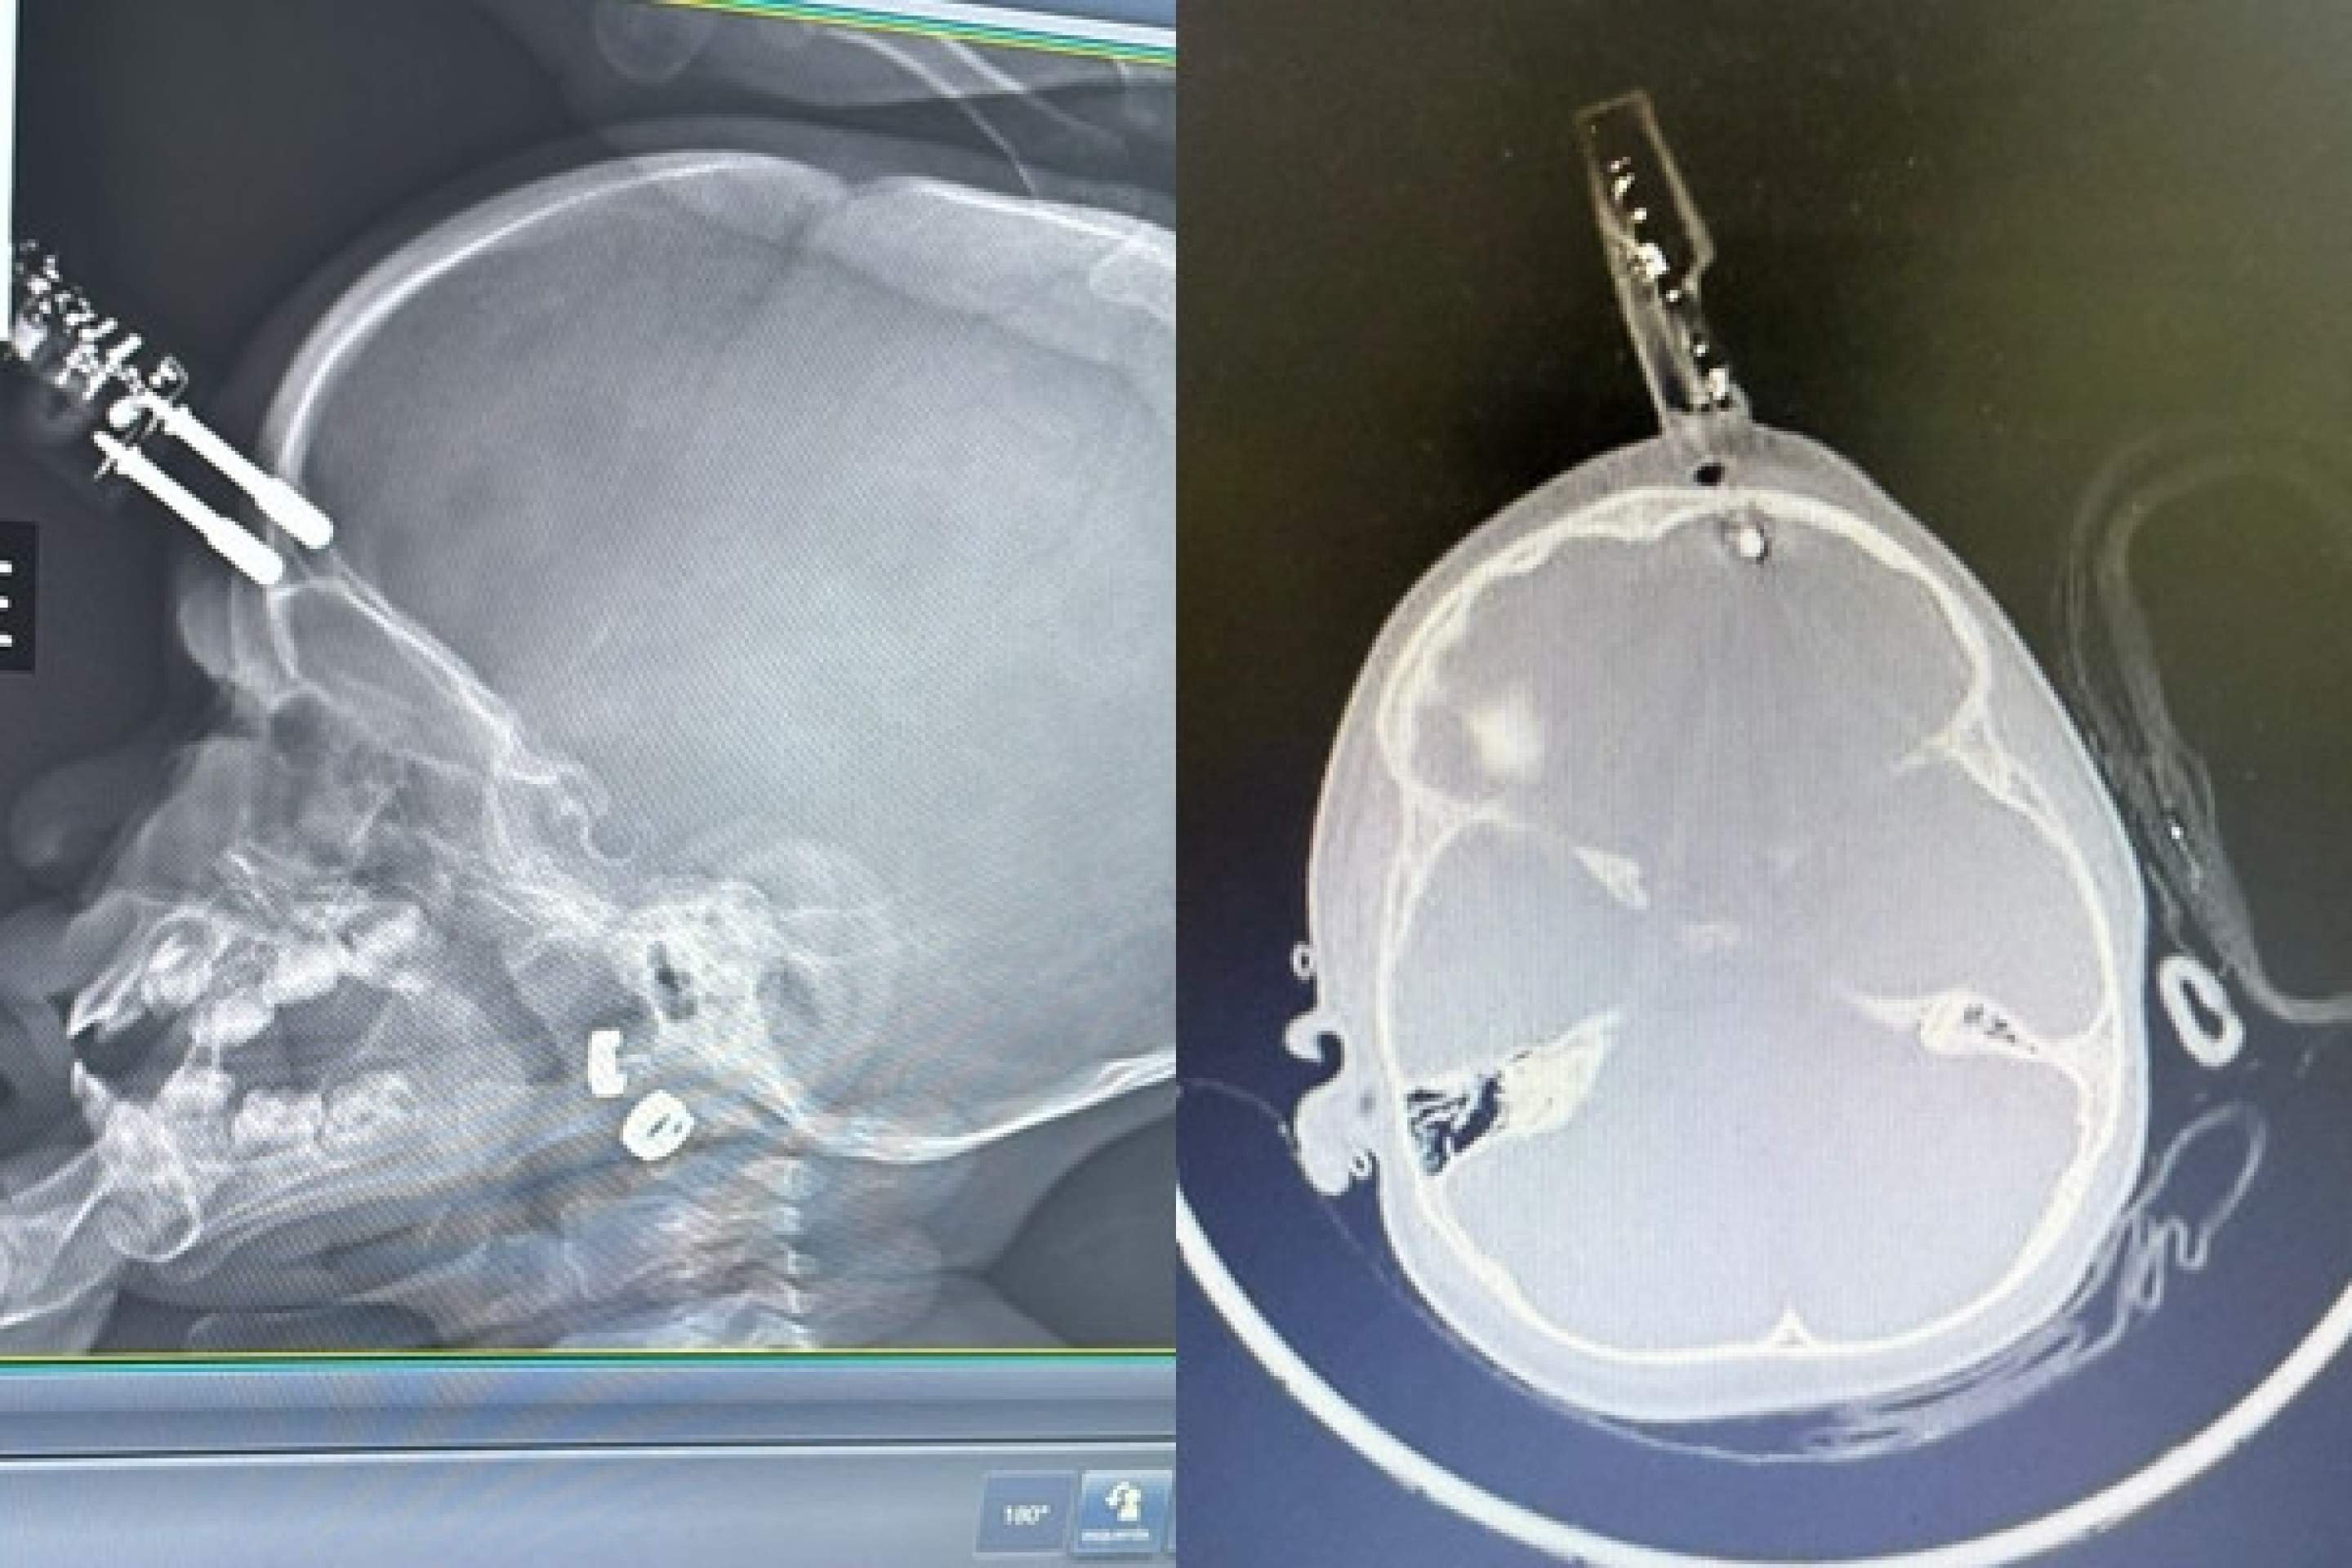

A criança foi levada inicialmente para a UPA de Divinópolis e, diante da gravidade, transferida pelo Samu para a sala vermelha do Hospital São João de Deus. Exames de imagem confirmaram que o pino havia transfixado o osso do crânio e atingido o cérebro. “O osso do crânio nessa idade é muito fino, tem apenas alguns milímetros. Pela tomografia, vimos que o objeto atravessou a calota craniana e lesionou a ponta do lobo frontal”, detalhou Bruno Castro.

Apesar da gravidade do ferimento, a criança estava consciente e foi levada imediatamente ao centro cirúrgico. O procedimento ocorreu sem intercorrências. “Foi uma cirurgia rápida e tranquila. Retiramos o corpo estranho, estancamos um pequeno sangramento e fizemos a correção da lesão. Ela acordou bem da anestesia e foi encaminhada ao CTI pediátrico”, afirmou o neurocirurgião.

A criança permaneceu 36 horas em observação intensiva e, após nova tomografia sem sinais de sangramento intracraniano, seguiu para a enfermaria. Por protocolo, recebeu antibiótico venoso durante cinco dias para prevenir infecções.